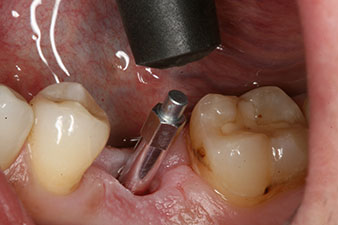

Implantat

Abb. 3: Nach Aufbereitung mit dem Implantmed Implantologiemotor wird ein Implantat (Durchmesser 4 mm, Länge 12 mm) bei einem Drehmoment von 43 Ncm maschinell eingeschraubt.

Nach gründlicher Entfernung des Granulationsgewebes wurde das Implantat wie geplant eingebracht (blueSky, bredent).